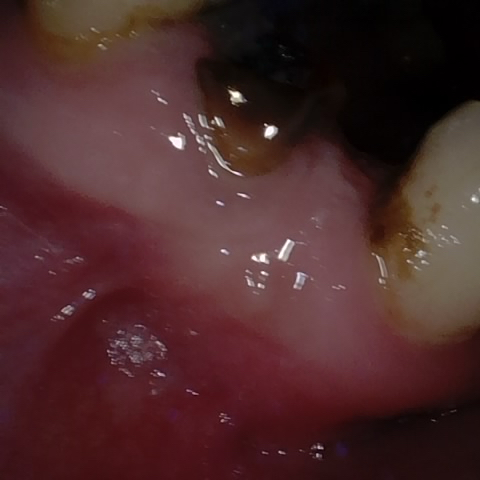

Annotated as "Good"